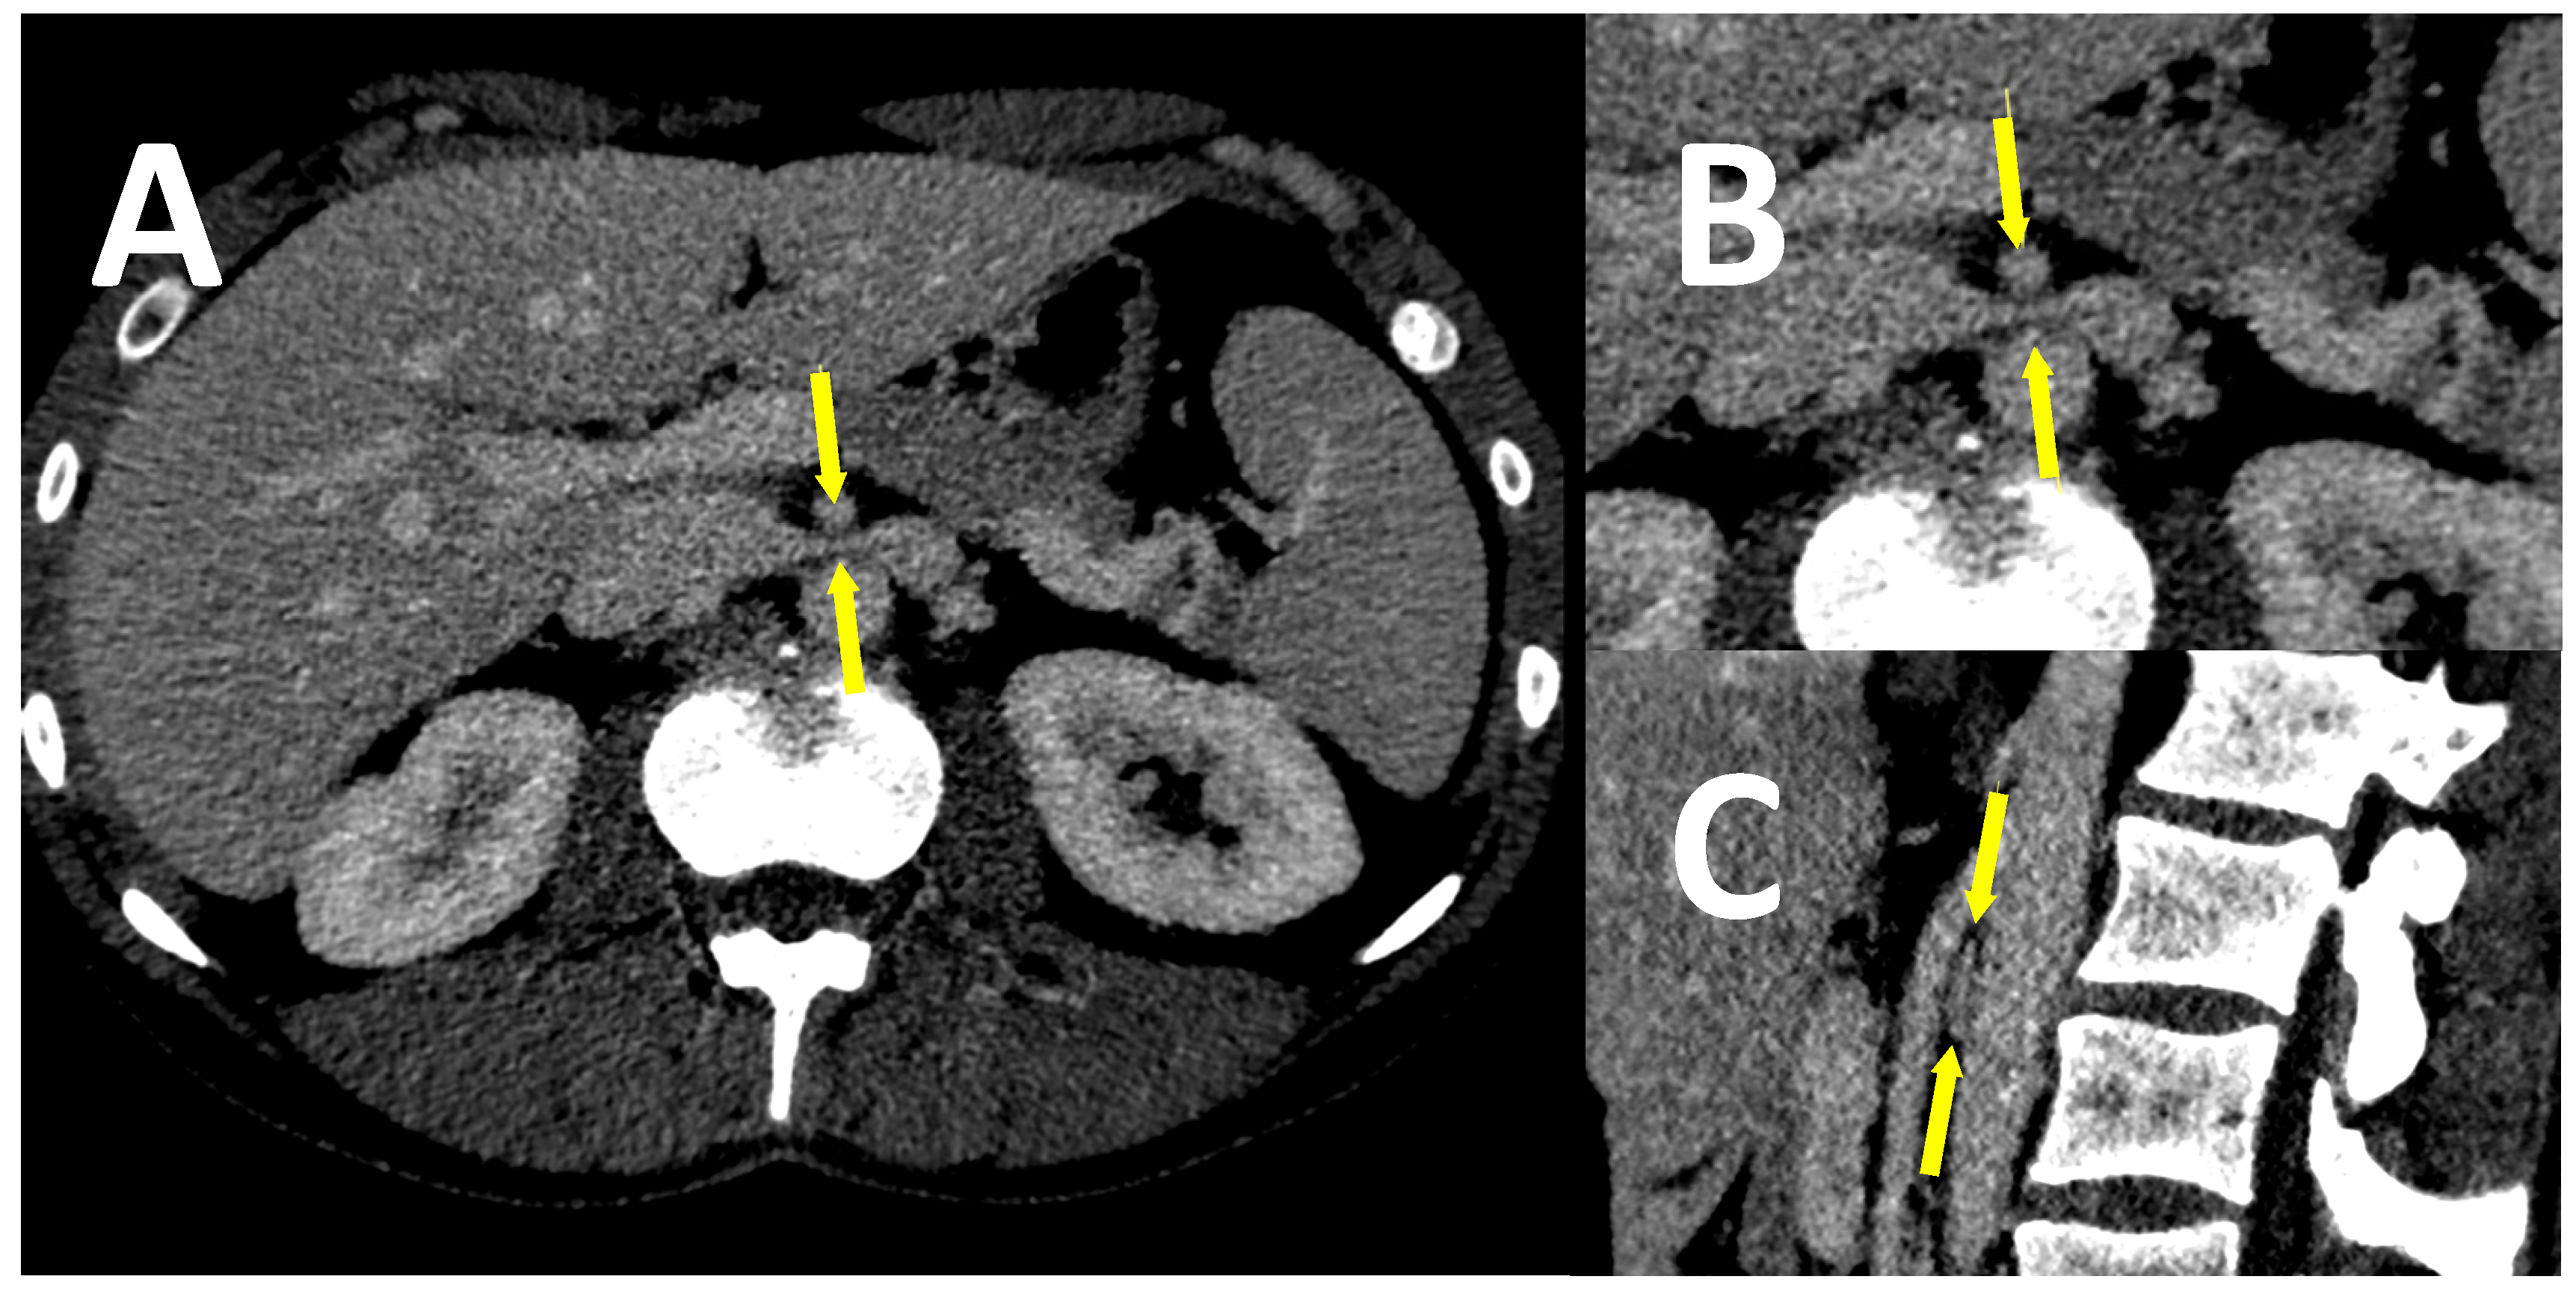

- Coakley, F.V.; Varghese, S.L.; Hricak, H. CT and MRI of pelvic varices in women. J. Comput. Assist. Tomogr. 1999, 23, 429–434. [Google Scholar] [CrossRef] [PubMed]

- Park, S.J.; Lim, J.W.; Ko, Y.T.; Lee, D.H.; Yoon, Y.; Oh, J.H.; Lee, H.K.; Huh, C.Y. Diagnosis of pelvic congestion syndrome using transabdominal and transvaginal sonography. AJR Am. J. Roentgenol. 2004, 182, 683–688. [Google Scholar] [CrossRef]

- Ganeshan, A.; Upponi, S.; Hon, L.Q.; Uthappa, M.C.; Warakaulle, D.R.; Uberoi, R. Chronic pelvic pain due to pelvic congestion syndrome: The role of diagnostic and interventional radiology. Cardiovasc. Intervent. Radiol. 2007, 30, 1105–1111. [Google Scholar] [CrossRef]

- Bookwalter, C.A.; VanBuren, W.M.; Neisen, M.J.; Bjarnason, H. Imaging appearance and nonsurgical management of pelvic venous congestion syndrome. Radiographics 2019, 39, 596–608. [Google Scholar] [CrossRef]